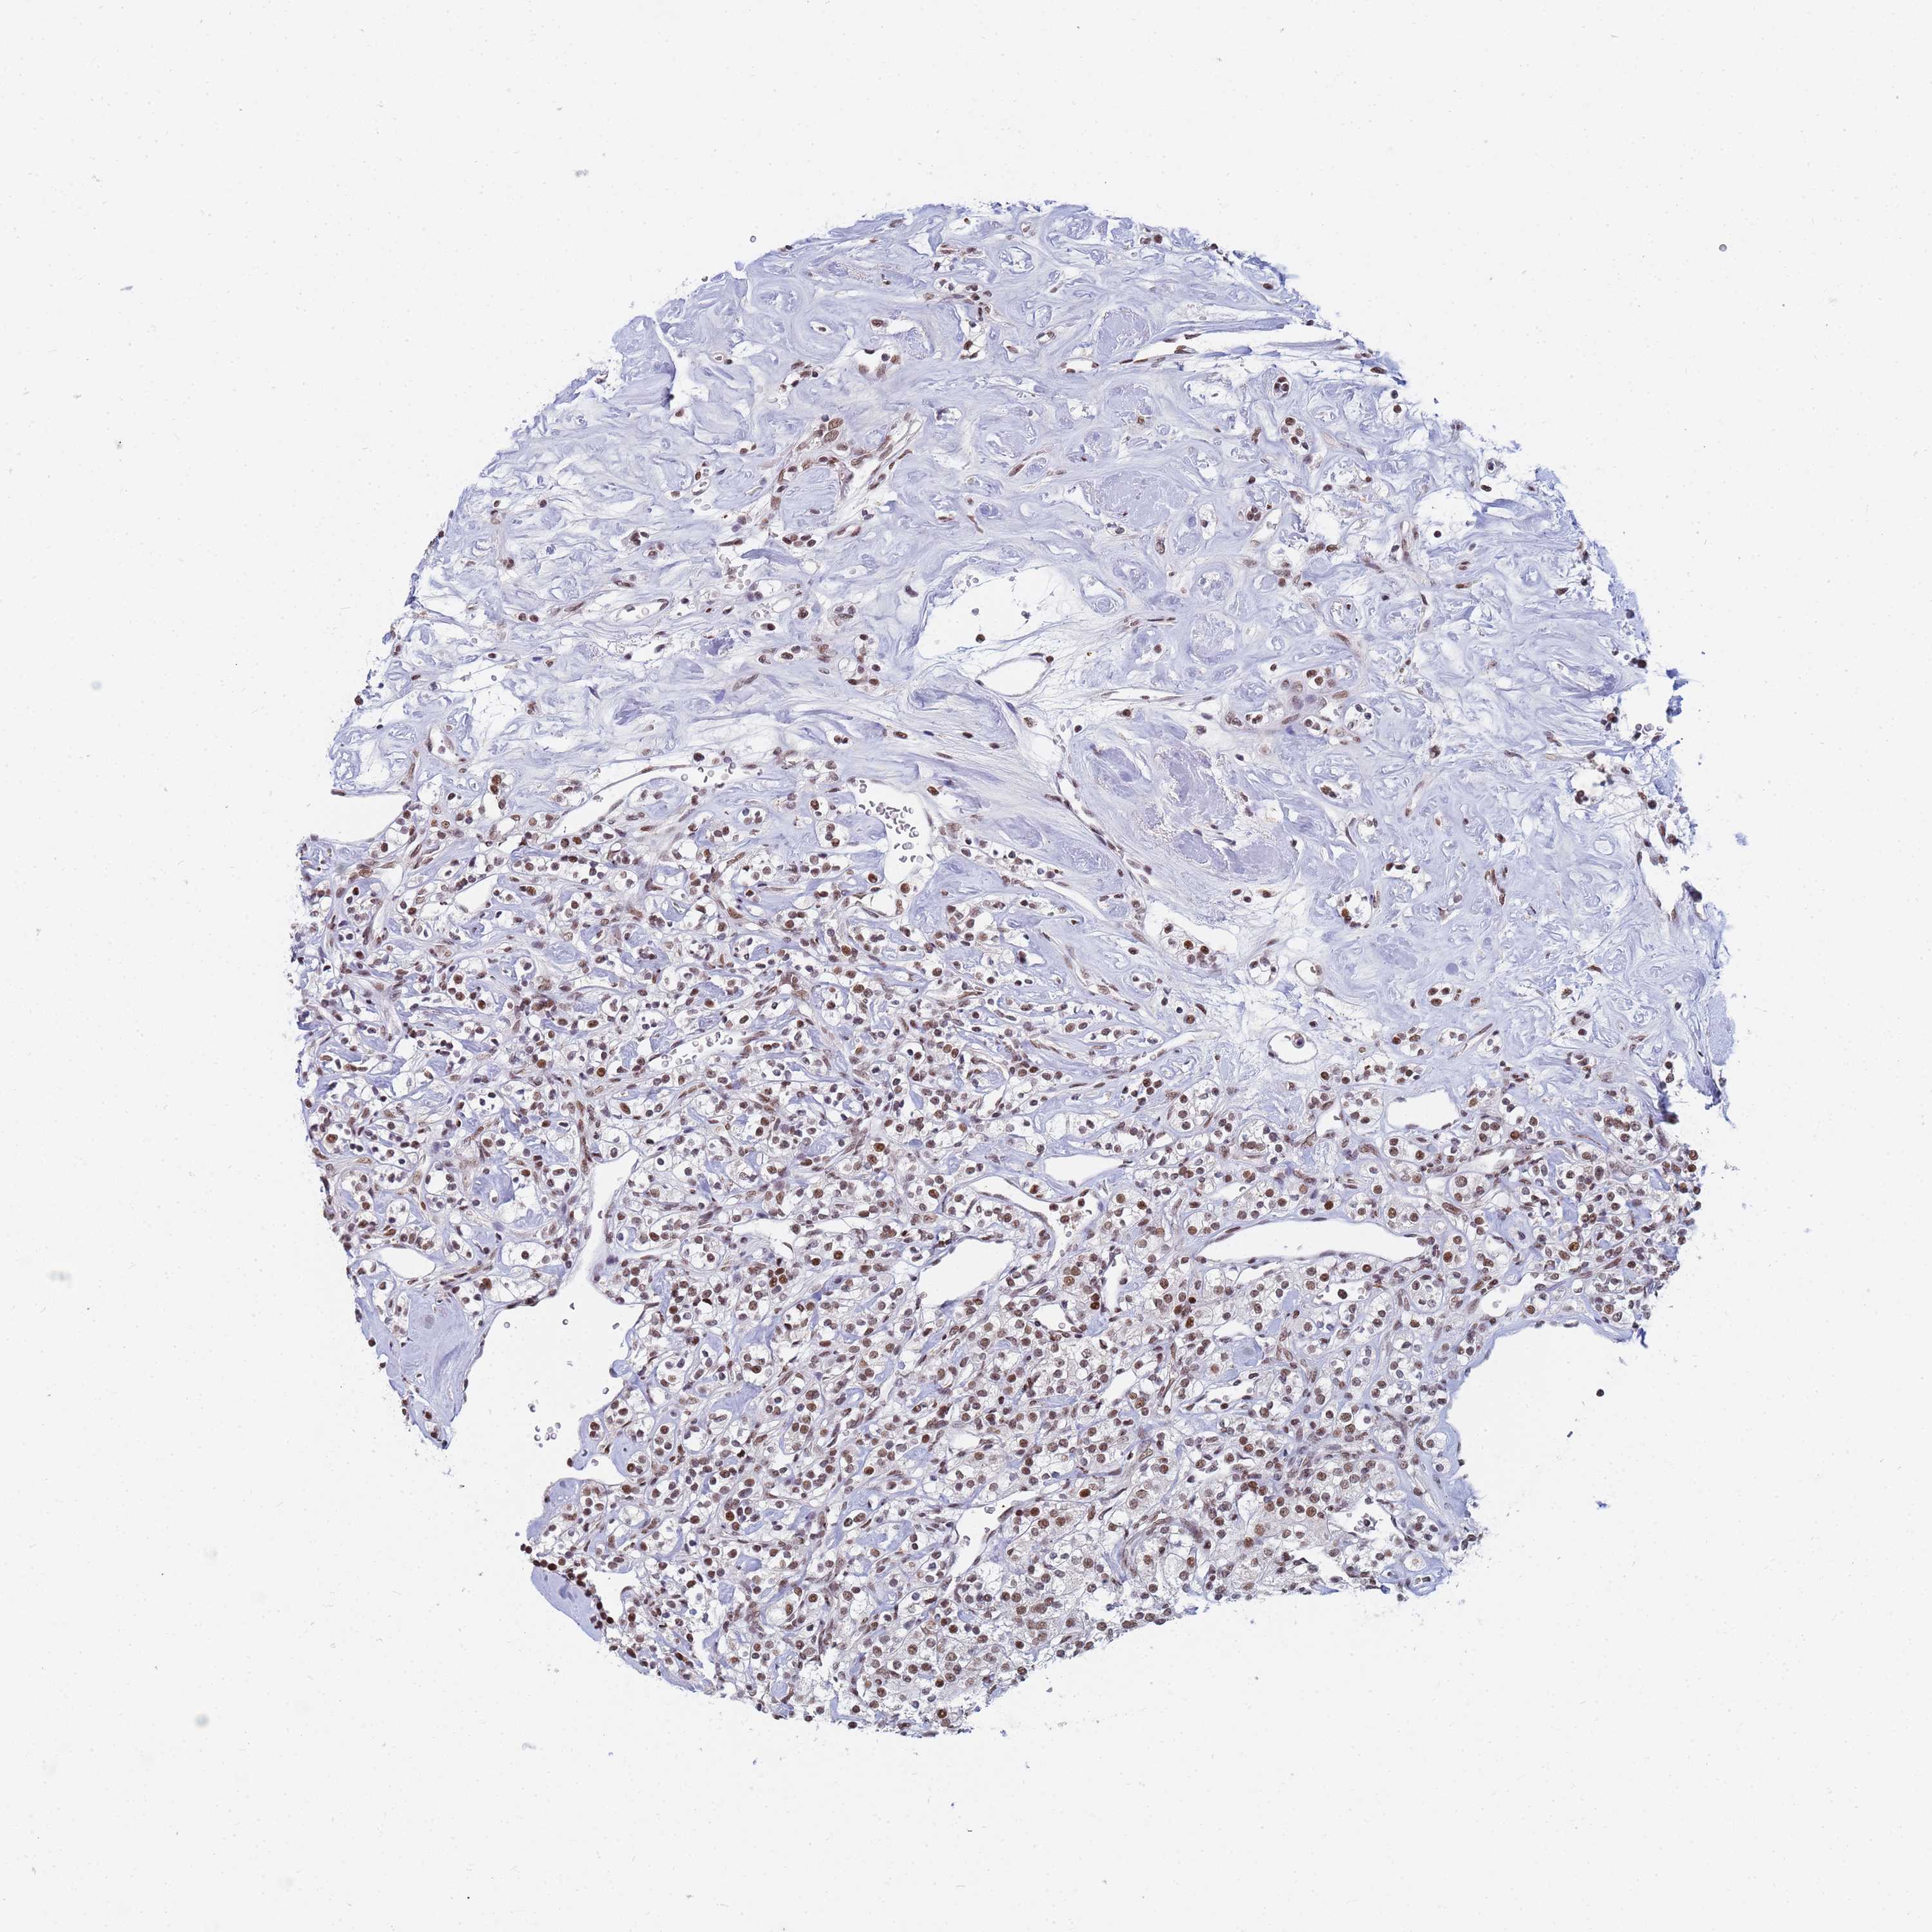

CANCER RENAL CANCER Show tissue menu

KICH TCGA KIRC TCGA KIRC VALIDATION KIRP TCGA PROTEIN RCC CPTAC PROTEIN EXPRESSION